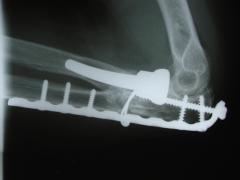

Περίπτωση 1ου ασθενούς

Προεγχειρητική

4 χρόνια μετά το χειρουργείο